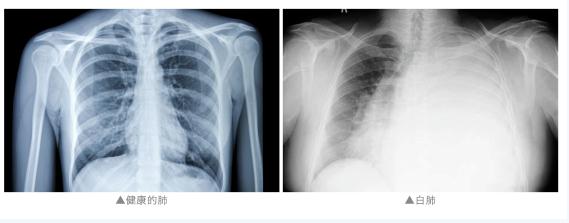

“两个肺都是白的,

发现的时候是甲流,

而且是混合感染。”

最终导致“白肺”

通常来说

“白肺”是指急性呼吸窘迫综合征

主要发生在重症感染时

双肺弥漫性病变进展迅速